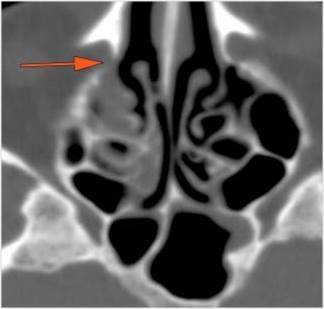

The orbital apex and the superior and inferior orbital fissures are infiltrated